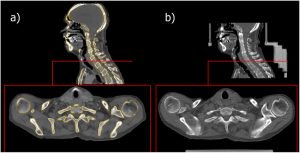

Ifoto ya 2D n’ifoto ya 3D

Ishusho y’umutima igaragaza neza itandukaniro riri hagati y’image en 2D n’image en 3D iri hejuru.

Image en 2D (ibumoso): igaragaza umutima mu buryo bworoshye, flat, nta bujyakuzimu. Ubonamo gusa imiterere y’inyuma n’utuyoboro tw’ingenzi, ariko ntubona uko chambers n’imitsi bihagaze mu buryo burambuye.

Image en 3D (iburyo): igaragaza umutima mu buryo bufite ubujyakuzimu, texture, n’imiterere y’imbere. Ubonamo neza imitsi, amaraso, n’utugingo twose mu mpande zitandukanye, bigafasha muganga kubona uko umutima wubatanye mu mubiri.

Mu magambo arambuye: Ifoto ya 2D ni ishusho yoroheje igaragaza gusa ubugari n’uburebure, naho ifoto ya 3D ikongeraho ubujyakuzimu, ikerekana ibintu mu buryo bw’imbere kandi ikaboneka mu mpande zitandukanye. Ni yo mpamvu CT Scan itanga amakuru arambuye cyane kurusha radiographie.